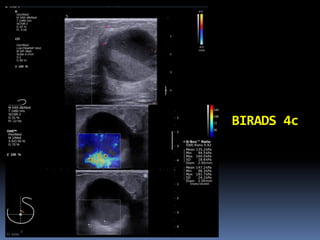

What BIRADS 3 or 4?

45y/o with lump in the left

breast

BIRADS 0

BIRADS 4c